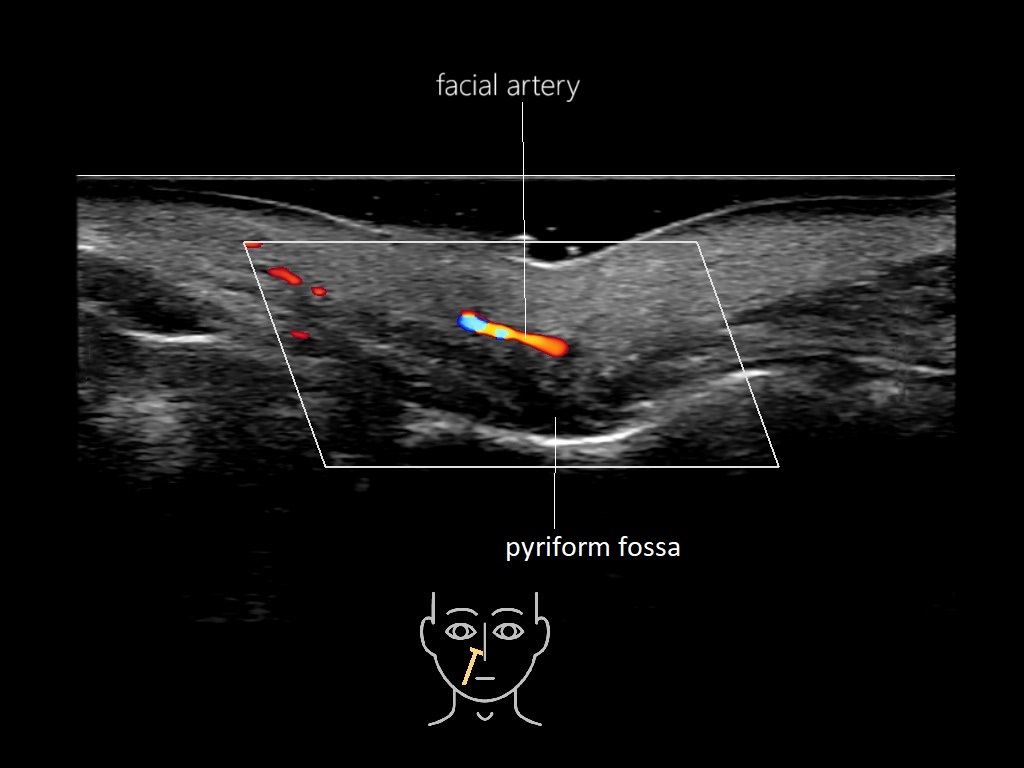

Study the first image to recognize the different layers. If you are sure about the layers, swipe to the second image to view the answer (if applicable).